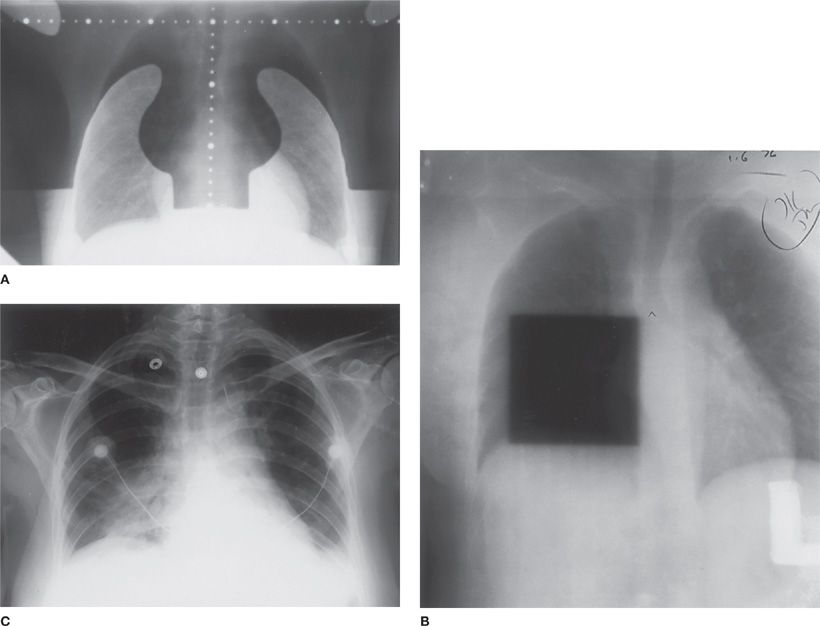

From thoracickey.com

Radiation Pneumonitis Thoracic Key Radiation Pneumonitis Signs And Symptoms What are the symptoms of pneumonitis? Radiation pneumonitis is a clinical diagnosis based on the history of radiation, imaging findings, and the presence of classic. This article describes the symptoms, factors. A general feeling of discomfort or illness (called malaise) shortness of breath. Symptoms of radiation pneumonitis include: Some people who have radiation therapy to the chest, such as for. Radiation Pneumonitis Signs And Symptoms.

Radiation Pneumonitis Thoracic Key Radiation Pneumonitis Signs And Symptoms Some people who have radiation therapy to the chest, such as for breast or lung cancer, may. What are the symptoms of pneumonitis? Symptoms of radiation pneumonitis include: This article describes the symptoms, factors. Radiation pneumonitis (rp) is an inflammation of the lungs due to radiation therapy or. A general feeling of discomfort or illness (called malaise) shortness of breath.. Radiation Pneumonitis Signs And Symptoms.